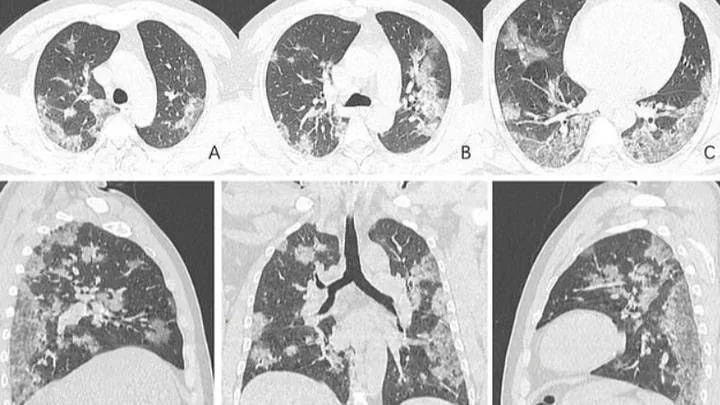

В России зумеры массово попадают в больницы от вейпа Попкорновая болезнь накрывает вейперов России. За последний год число заболевших выросло на 30%. Пульмонологи фиксируют резкий рост тяжёлых заболеваний лёгких среди подростков и молодёжи до 35 лет, которые на регулярной основе курят электронные сигареты. Всё дело в веществе 2,3-бутандионе. Раньше это вещество добавляли только в вейпы с ТГК, чтобы создавать определённый вкус попкорна, но недавно русские производители жижи стали добавлять это вещество во все фруктовые вкусы для создания яркости. Изменения лёгких при вдыхании фатальны. Сначала…